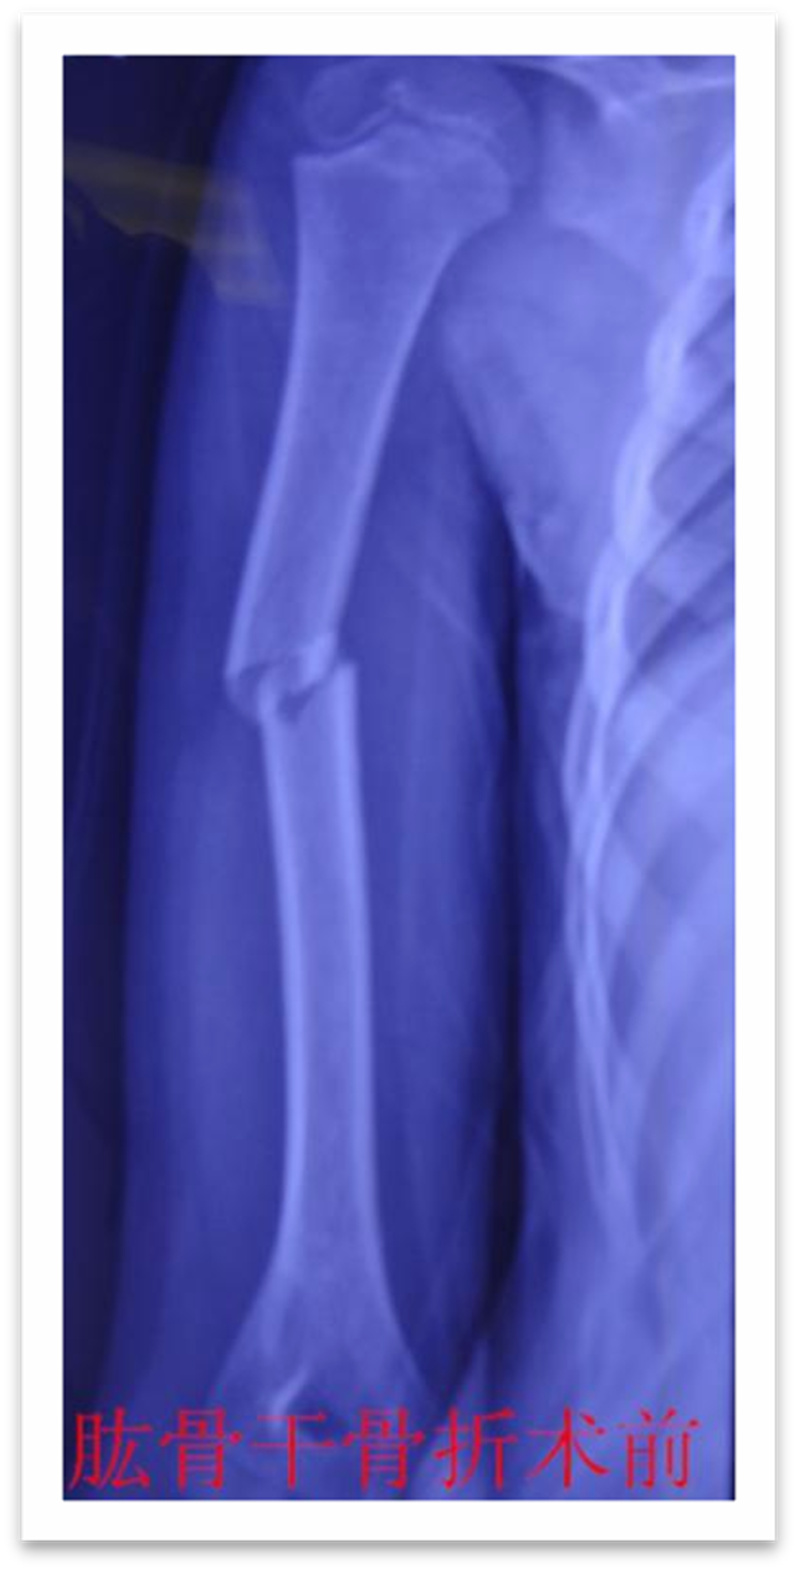

,弹性髓内钉内固定解决了这个矛盾。有人说,弹性髓内钉的出现是上天对儿童的恩惠。的确,弹性髓内钉是治疗小儿长管状骨骨骨折的一种理想、可靠的内固定方法。弹性髓内钉技术发源于法国,在欧洲广泛应用后,现已为全球所接受,被称为是儿童骨科界的一次革命。徐州儿童医院骨一科应用弹性髓内钉技术治疗四肢长管状骨骨折,具有创伤小、恢复快、并发症相对少,孩子能较快恢复正常生活、学习等优点。该技术先将骨折闭合复位,通过微小的切口将特制的弹性髓内钉置入骨髓腔,达到固定骨折的目的。适用于肱骨,股骨,尺桡骨等部位的常见骨折(图)。